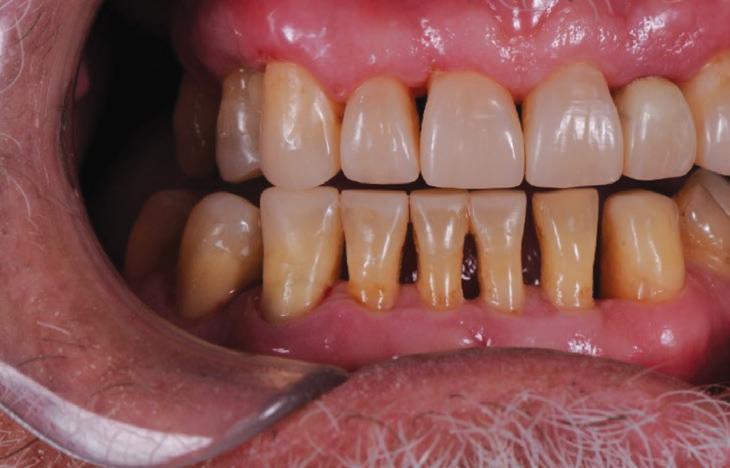

This gentleman presented with pain in his upper left quadrant. He had not been to a Dentist for many years and his dental experience had primarily been to have problematic teeth extracted (Fig. 1). As a result, he no longer had any of his molar teeth, but had been functioning well with his remaining premolar occlusion.

After his examination appointment, it was clear that the two premolars in the upper left quadrant had significant apical pathology and could not be predictably treated. His remaining dentition showed generalised attrition subsequent to dental erosion from gastric reflux, and his lower anteriors showed recession and some loss of periodontal support (Figs. 2, 3).